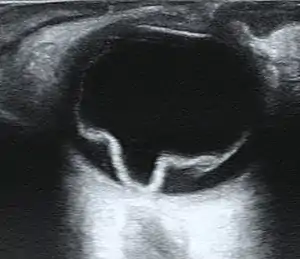

Imaging

Ultrasound, MRI, and CT scan are commonly used to diagnose retinal detachment.